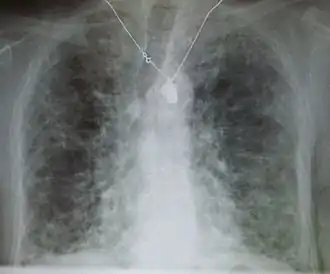

Lung

Side effects of oral amiodarone at doses of 400 mg or higher include various pulmonary effects.[44] The most serious reaction is interstitial lung disease. Risk factors include high cumulative dose, more than 400 milligrams per day, duration over two months, increased age, and preexisting pulmonary disease. Some individuals were noted to develop pulmonary fibrosis after a week of treatment, while others did not develop it after years of continuous use.[44] Common practice is to avoid the agent if possible in individuals with decreased lung function.

The most specific test of pulmonary toxicity due to amiodarone is a dramatically decreased DLCO noted on pulmonary function testing.